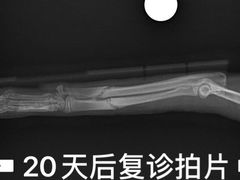

• 爱侣宠医·鹦鹉专科·小型哺乳类·异宠专科(灵石路店)